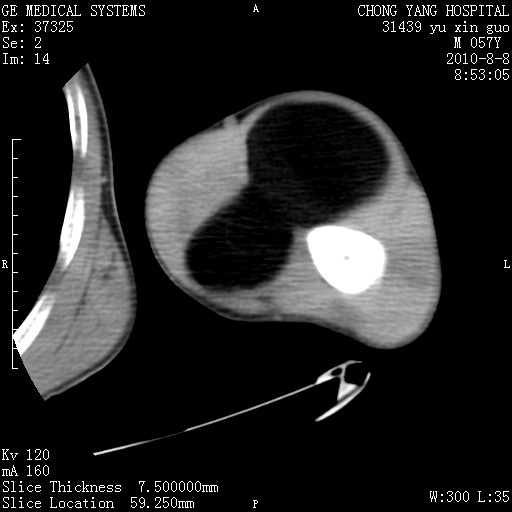

标题: CT28267:M57Y 上臂包块8年余。 [打印本页]

标题: CT28267:M57Y 上臂包块8年余。

上臂软组织内脂肪瘤。

软组织内脂肪瘤

包膜光滑、完整的脂肪密度肿块,支持脂肪瘤。